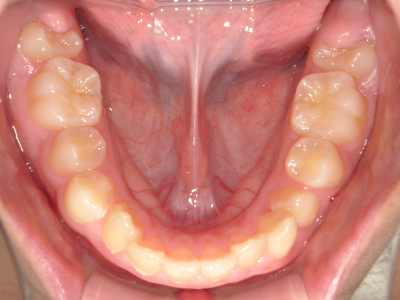

歯並びの相談に来られるお子様は、口呼吸をしているケースが多く、これが歯並びに大きな影響を与えています。

↓ - 下あごが狭くなる・下あごの位置が悪くなる

↓ - さまざまな不正咬合が生じる

ないき歯科クリニックでは、上あごの成長不足を補い、鼻呼吸を獲得しつつ歯列を整え、将来のお口をより健康な状態にすることをゴールに定める矯正治療をおこなっています。